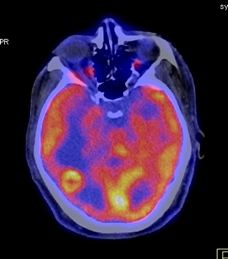

Trong chẩn đoán di căn não, dược chất phóng xạ thường được sử dụng là TC-99m. Trường hợp điển hình: hình ảnh tổn thương tăng hoạt tính phóng xạ.

Theo Virani (2009); Virani (2009) thì độ nhạy của FDG-PET/CT trong việc phát hiện di căn não là 97,8% so với chụp cộng hưởng từ sọ não, có 35,9% bệnh nhân không có triệu chứng thần kinh được phát hiện di căn não bằng FDG-PET/CT.

Hình 7. Hình ảnh di căn não của bệnh nhân ung thư phổi không phải tế bào nhỏ được phát hiện trên PET/CT tại Trung tâm Y học hạt nhân và ung bướu, Bệnh viện Bạch Mai.